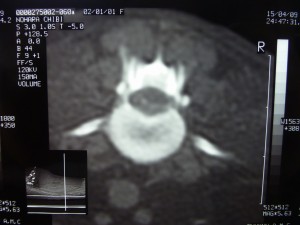

4月10日朝のカキコを見つけました。当初、9日PM11:00手術開始予定でした。その後、予定が変更あったようです。そのため、小生動揺したみたいですね。チビタの造影CTの画像です。拡大した画像が手術したところだと思うんですがね。間違っていたら恥ずかしいですね。

手術、終わった当日朝のカキコです。。その後の回復見ると。。手術は、だい、大成功でした。。かんしゃ。感謝です。。ほんと、緊急手術してもらってよかったあ。。。けど、電話でCT画像の話しても、正直よくわからなかったですね。。